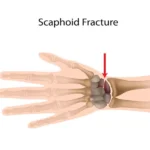

استخوان اسکافویید یکی از مهمترین استخوانهای مچ دست است که بین دو ردیف استخوانهای کارپ قرار دارد و نقش حیاتی در ثبات و حرکت مچ دارد. شکستگی این استخوان، اگرچه ممکن است کوچک بهنظر برسد، اما در صورت درمان نشدن صحیح، میتواند منجر به درد مزمن، کاهش دامنه حرکت و حتی آرتروز مچ شود.

اسکافویید یکی از استخوانهای ردیف اول مچ دست است که در سمت شست قرار دارد. این استخوان به دلیل موقعیتش، رابط بین ساعد و استخوانهای دیگر مچ است و فشار زیادی را حین حرکات روزمره تحمل میکند.